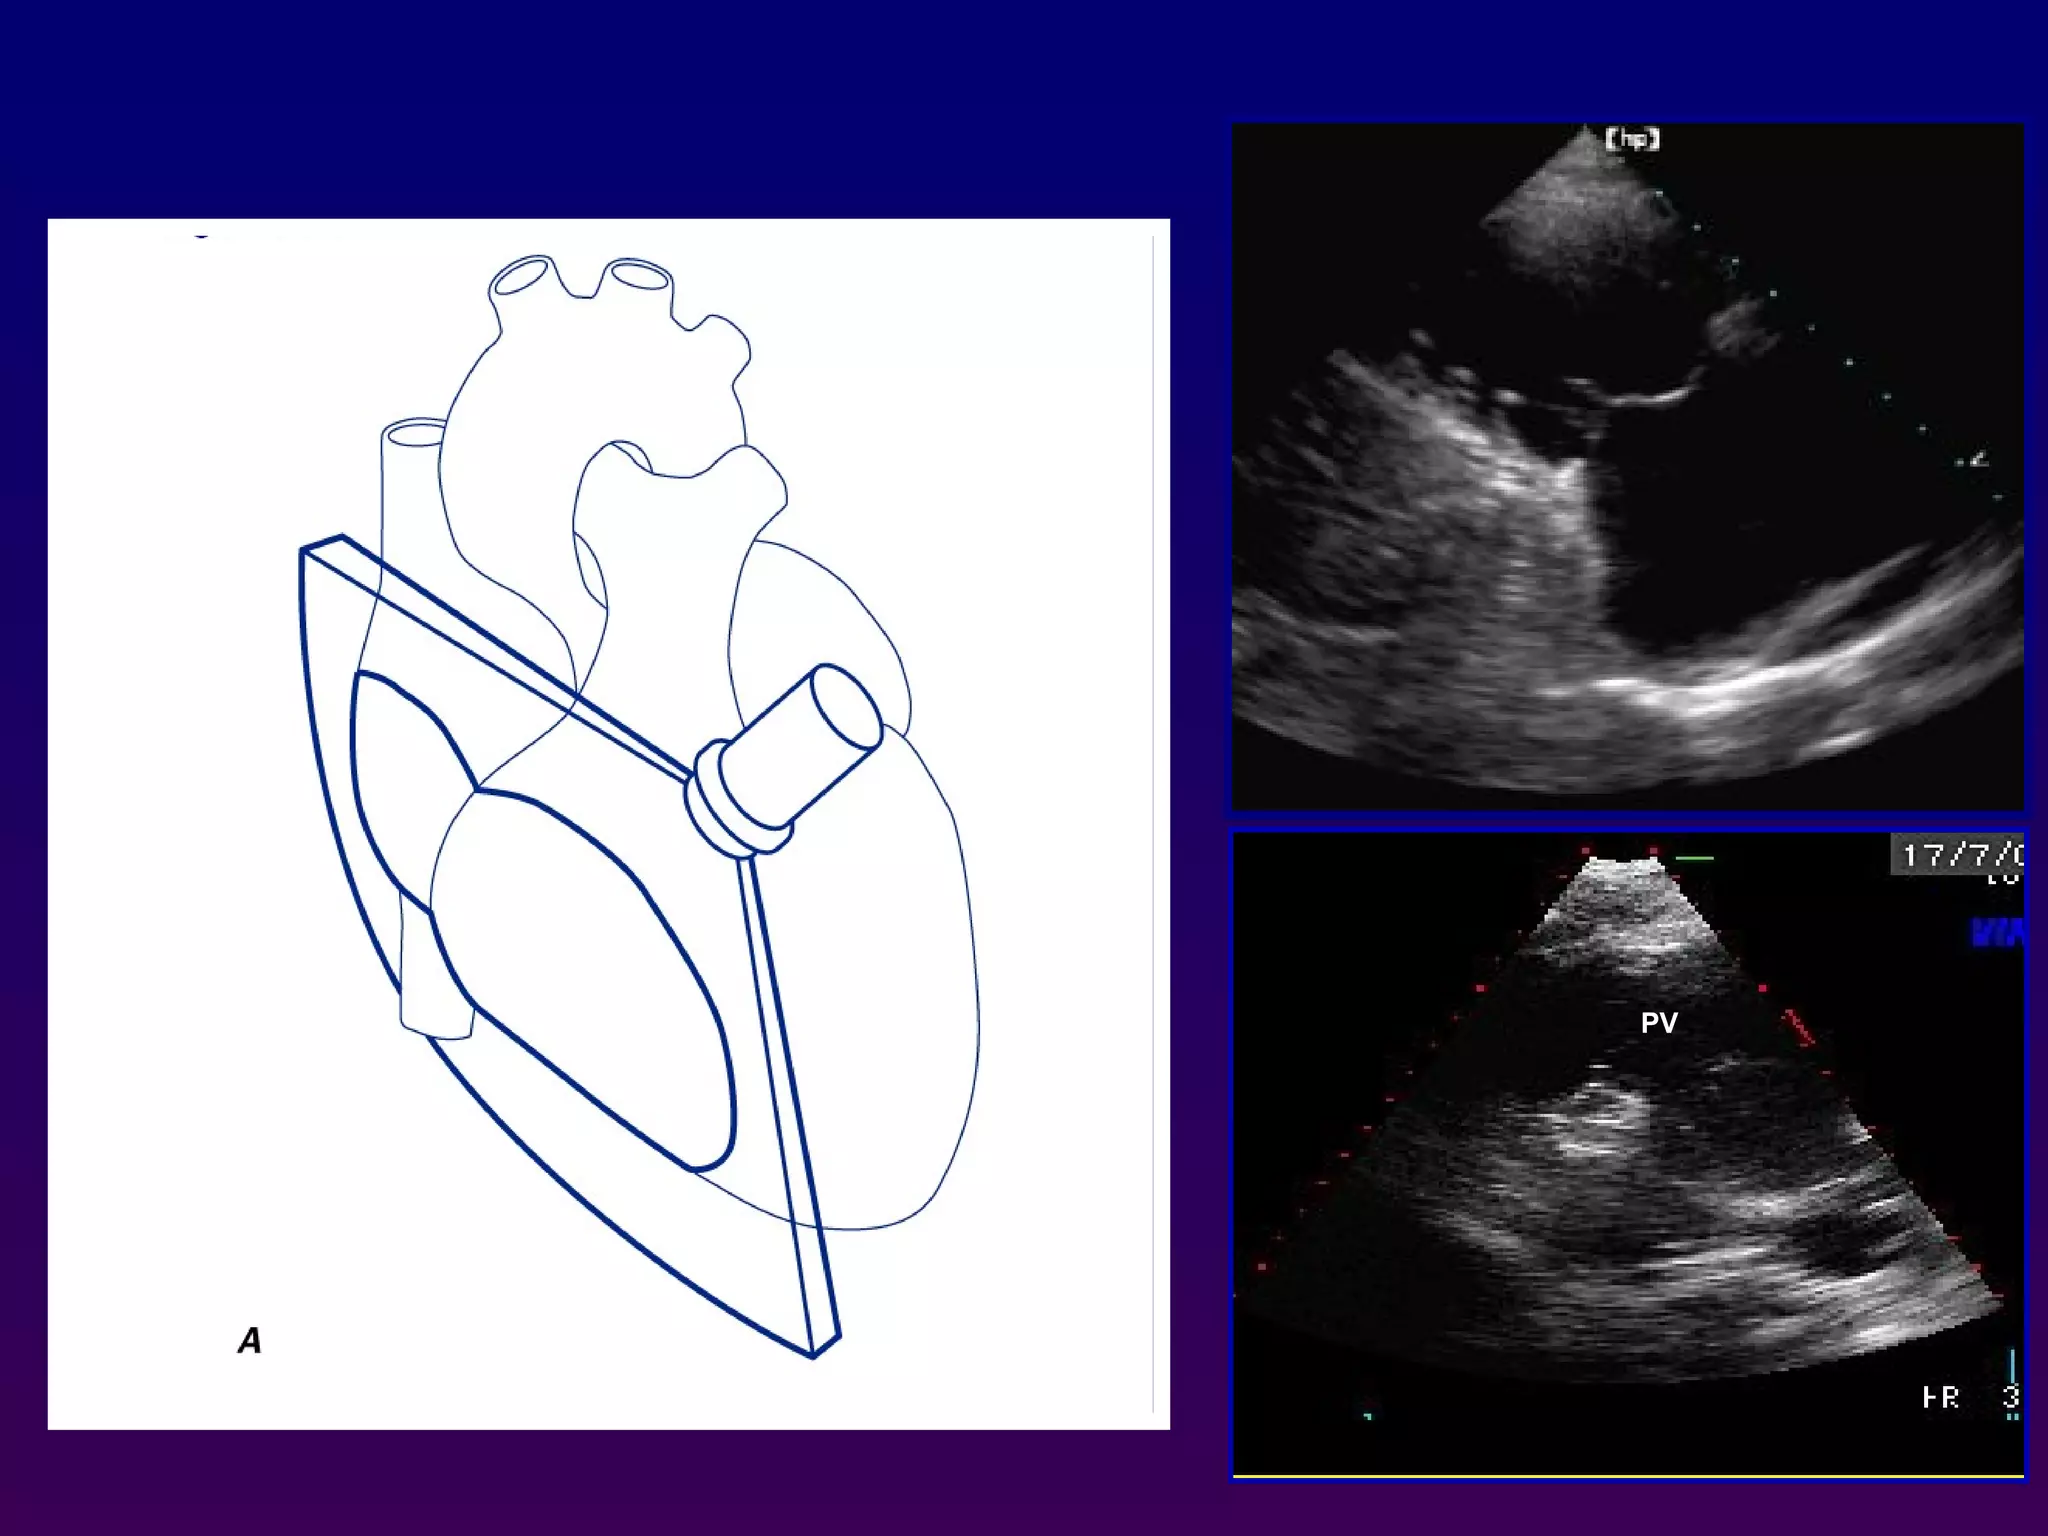

Right ventricular inflow and outflow

Inferomedial angulation from the parasternal long-axis

position is performed to obtain the "right ventricular

inflow" view which includes the right atrium,

coronary sinus, septal and anterior leaflets of the

tricuspid valve and basal right ventricle

•Superior angulation of the probe permits depiction

of the right ventricular outflow tract, including the

pulmonic valve and main pulmonary artery.

Right ventricular inflowand outflow Inferomedial angulation from the parasternal long-axis position is performed to obtain the "right ventricular inflow" view which includes the right atrium, coronary sinus, septal and anterior leaflets of the tricuspid valve and basal right ventricle •Superior angulation of the probe permits depiction of the right ventricular outflow tract, including the pulmonic valve and main pulmonary artery. PVTV RA